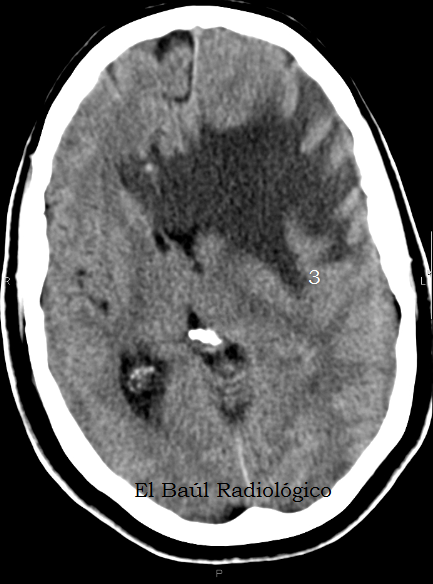

IMÁGENES SIN CONTRASTE ENDOVENOSO

Todas las exploraciones de Tomografía Computarizada craneoencefálica deben realizarse primero sin contraste endovenoso. Y, dependiendo de los hallazgos encontrados, se repite el examen despues de administrar una dosis de contraste. Si no se hace así podemos llevarnos alguna sorpresa.

FIGURA 4) Y más edema que desplaza las estructuras de la línea media en sentido contralateral. ¿....?

(And more edema which displaces the midline structures in the contralateral sense. ....?)